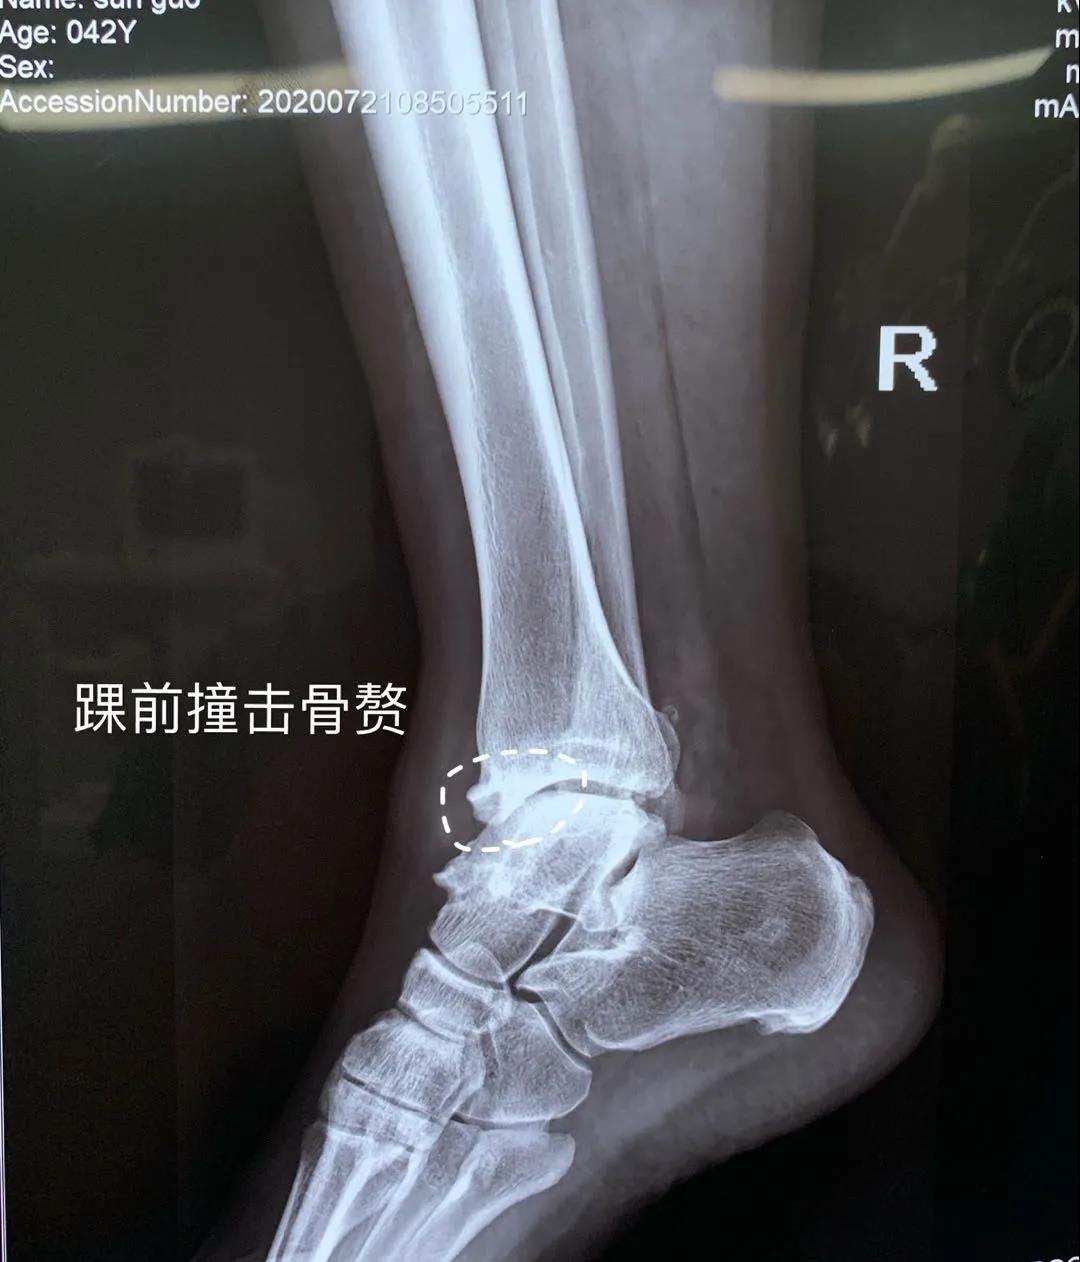

近日,醫(yī)院骨二科成功治療一位踝關(guān)節(jié)反復(fù)疼痛病人。患者李某,男,42歲,踝關(guān)節(jié)外傷導(dǎo)致外側(cè)韌帶損傷踝關(guān)節(jié)不穩(wěn),長(zhǎng)期沒(méi)有及時(shí)治療導(dǎo)致踝關(guān)節(jié)骨關(guān)節(jié)炎的發(fā)生。患者踝關(guān)節(jié)疼痛不能長(zhǎng)距離行走這是術(shù)前應(yīng)力位片提示踝關(guān)節(jié)距骨傾斜,踝關(guān)節(jié)踝前撞擊綜合癥,給予踝關(guān)節(jié)鏡下關(guān)節(jié)腔清理,骨贅切除,并給予外側(cè)韌帶重建恢復(fù)關(guān)節(jié)穩(wěn)定性。目前,患者手術(shù)后的踝關(guān)節(jié)穩(wěn)定,功能恢復(fù)良好,即將康復(fù)出院。